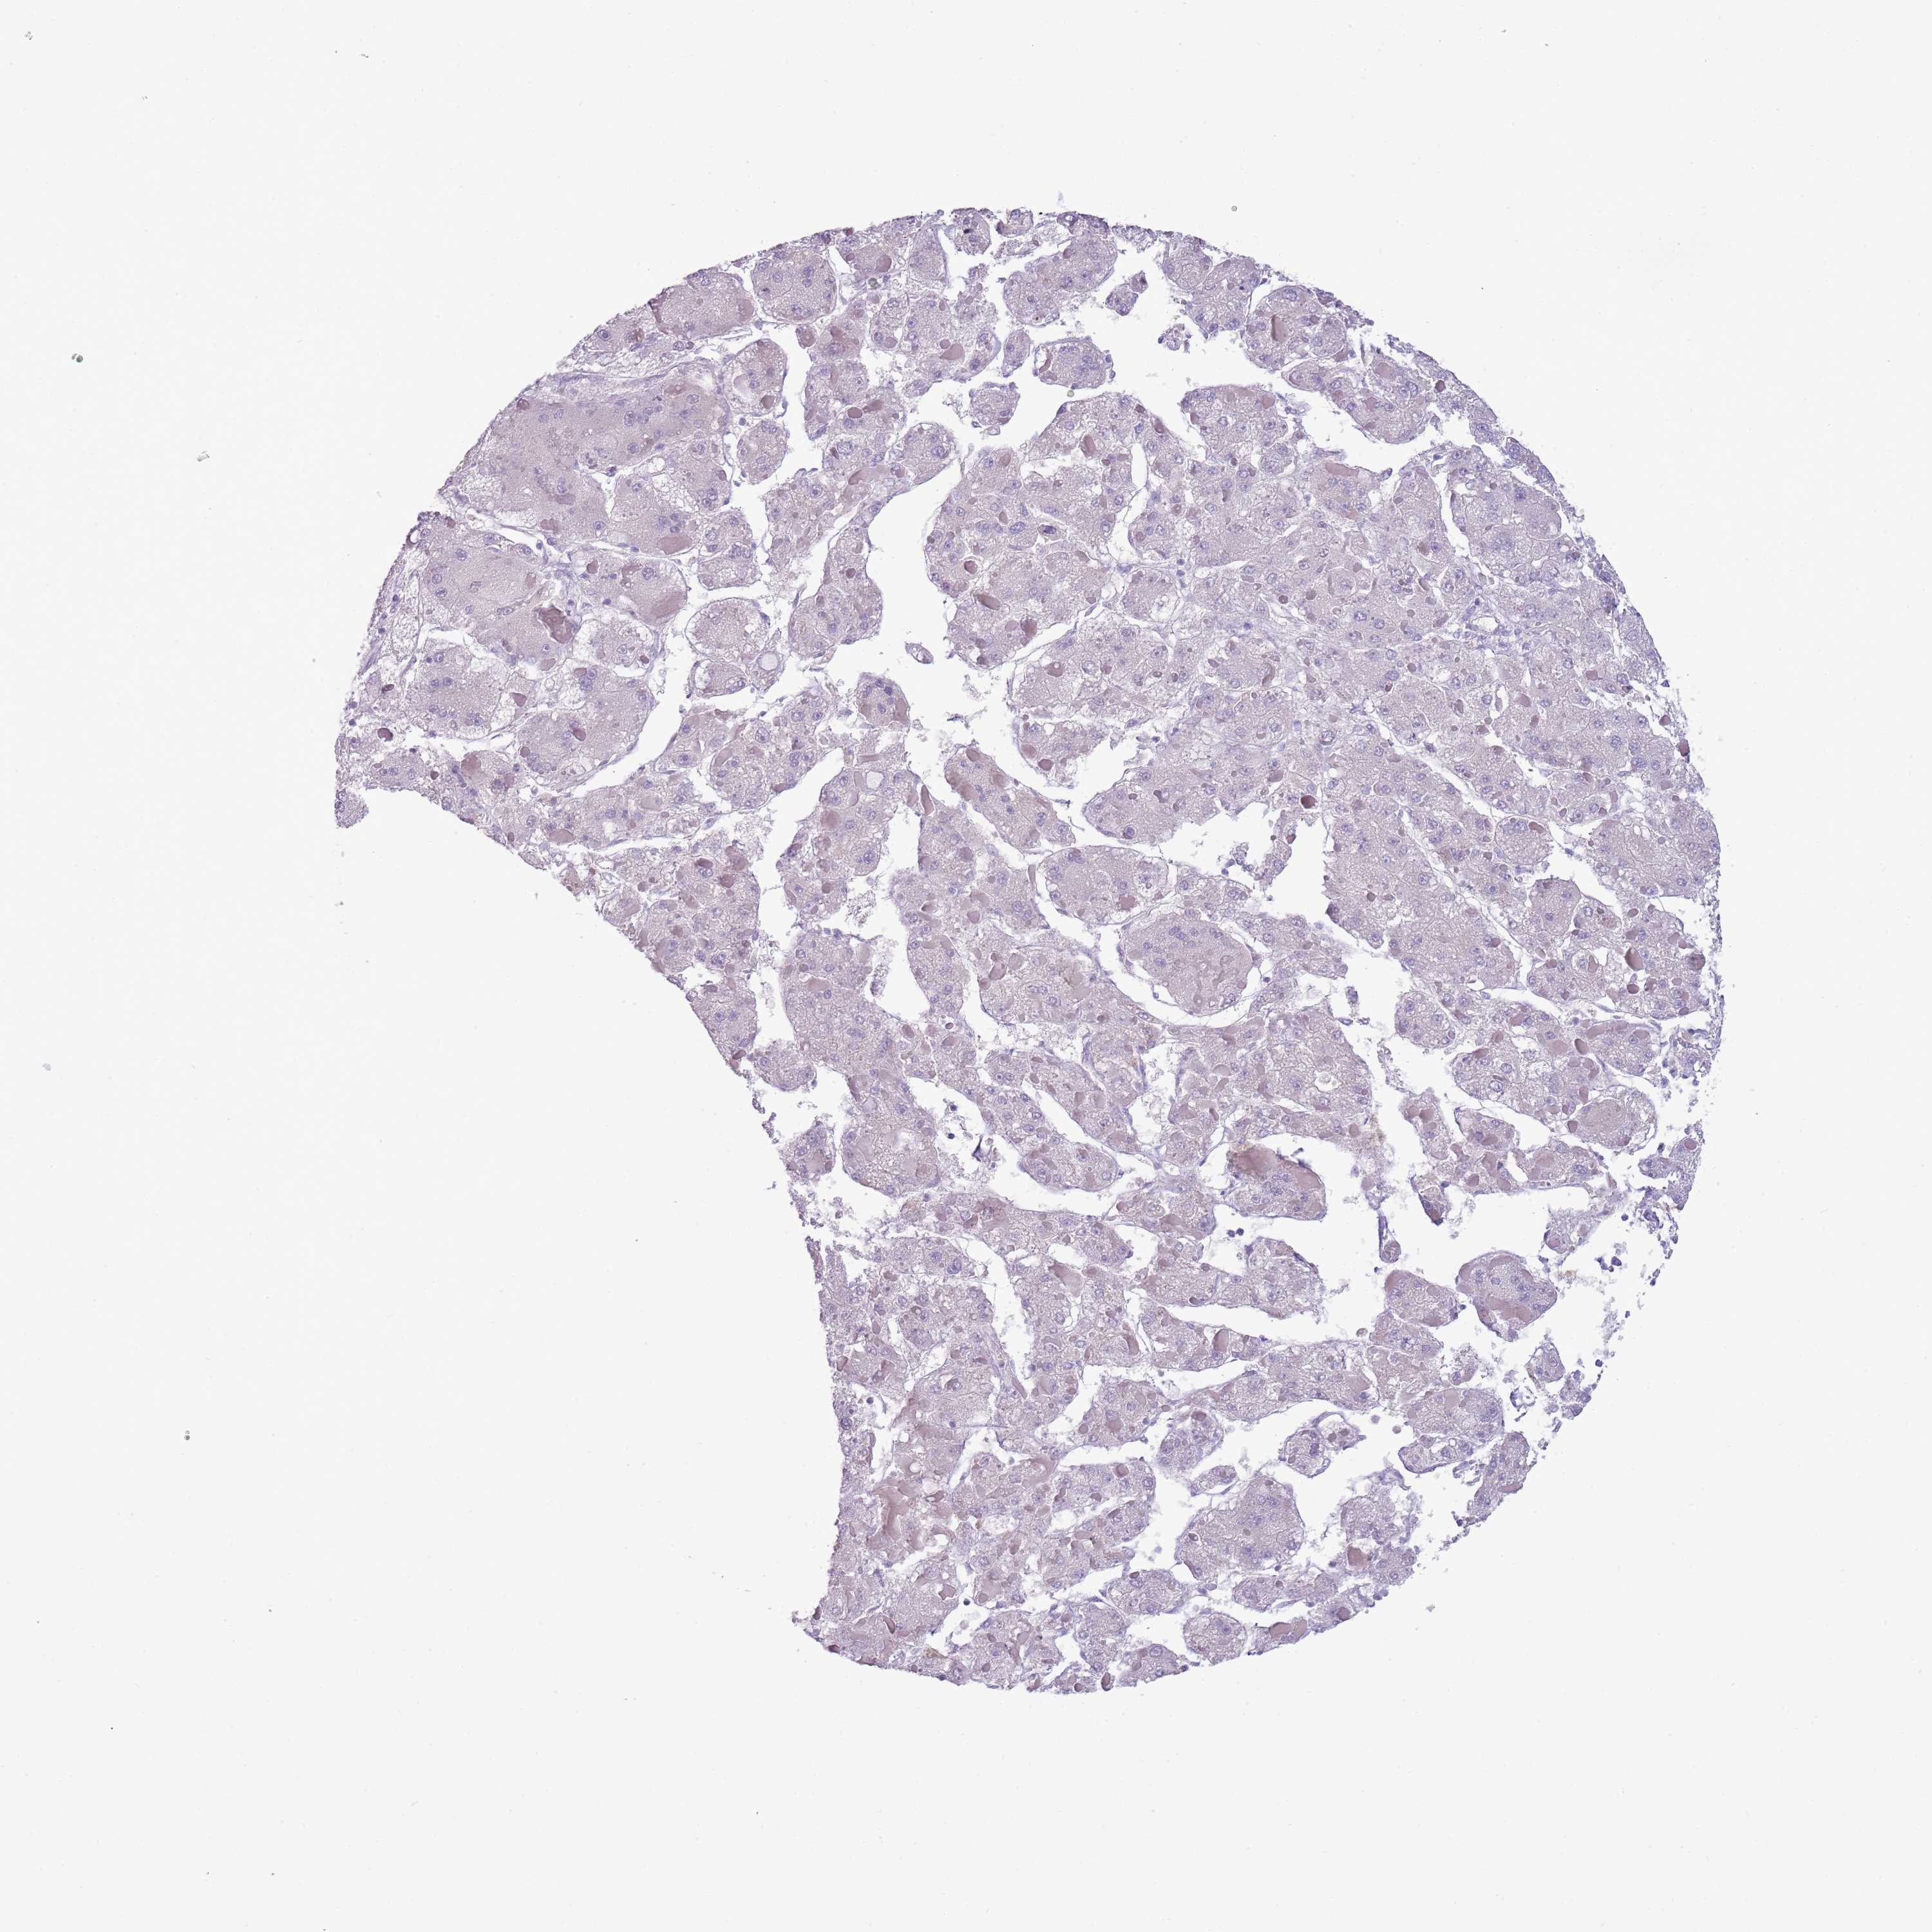

LIVER CANCER - Protein expressioni

A mouse-over function shows sample information and annotation data. Click on an image to view it in a full screen mode. Samples can be filtered based on level of antibody staining by selecting one or several of the following categories: high, medium, low and not detected. The assay and annotation is described here.

Note that samples used for immunohistochemistry by the Human Protein Atlas do not correspond to samples in the TCGA dataset.

Antibody stainingi

Antibody staining in the annotated cell types in the current human tissue is reported as not detected, low, medium, or high, based on conventional immunohistochemistry profiling in selected tissues. This score is based on the combination of the staining intensity and fraction of stained cells.

Each image is clickable and will lead to virtual microscopy that enables deeper exploration of all samples and also displays staining intensity scores, fraction scores and subcellular localization as well as patient and tissue information for each sample.

Antibody HPA045044

Antibody HPA046411

Antibody HPA047447

Antibody HPA058050

Cholangiocarcinoma

Carcinoma, Hepatocellular, NOS